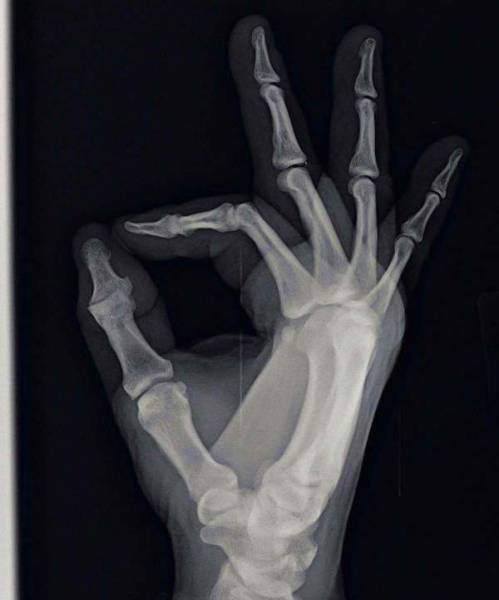

A crew in the finger.